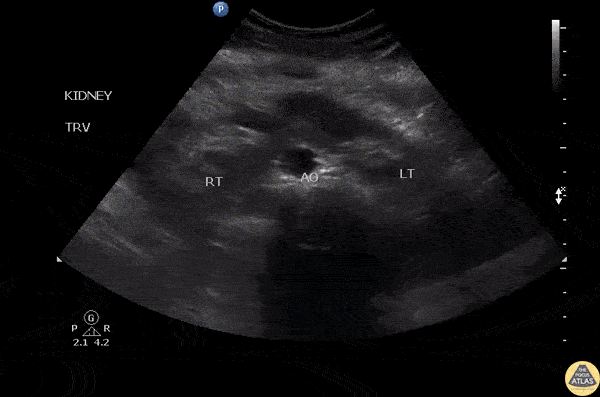

Renal/GU - Horseshoe Kidney

POCUS was used for evaluation of right flank pain with suspected hydronephrosis. A transabdominal view revealed obstructive uropathy due to a horseshoe kidney. Image courtesy of Robert Jones DO, FACEP @RJonesSonoEM Director, Emergency Ultrasound; MetroHealth Medical Center; Professor, Case Western Reserve Medical School, Cleveland, OH View his original post here